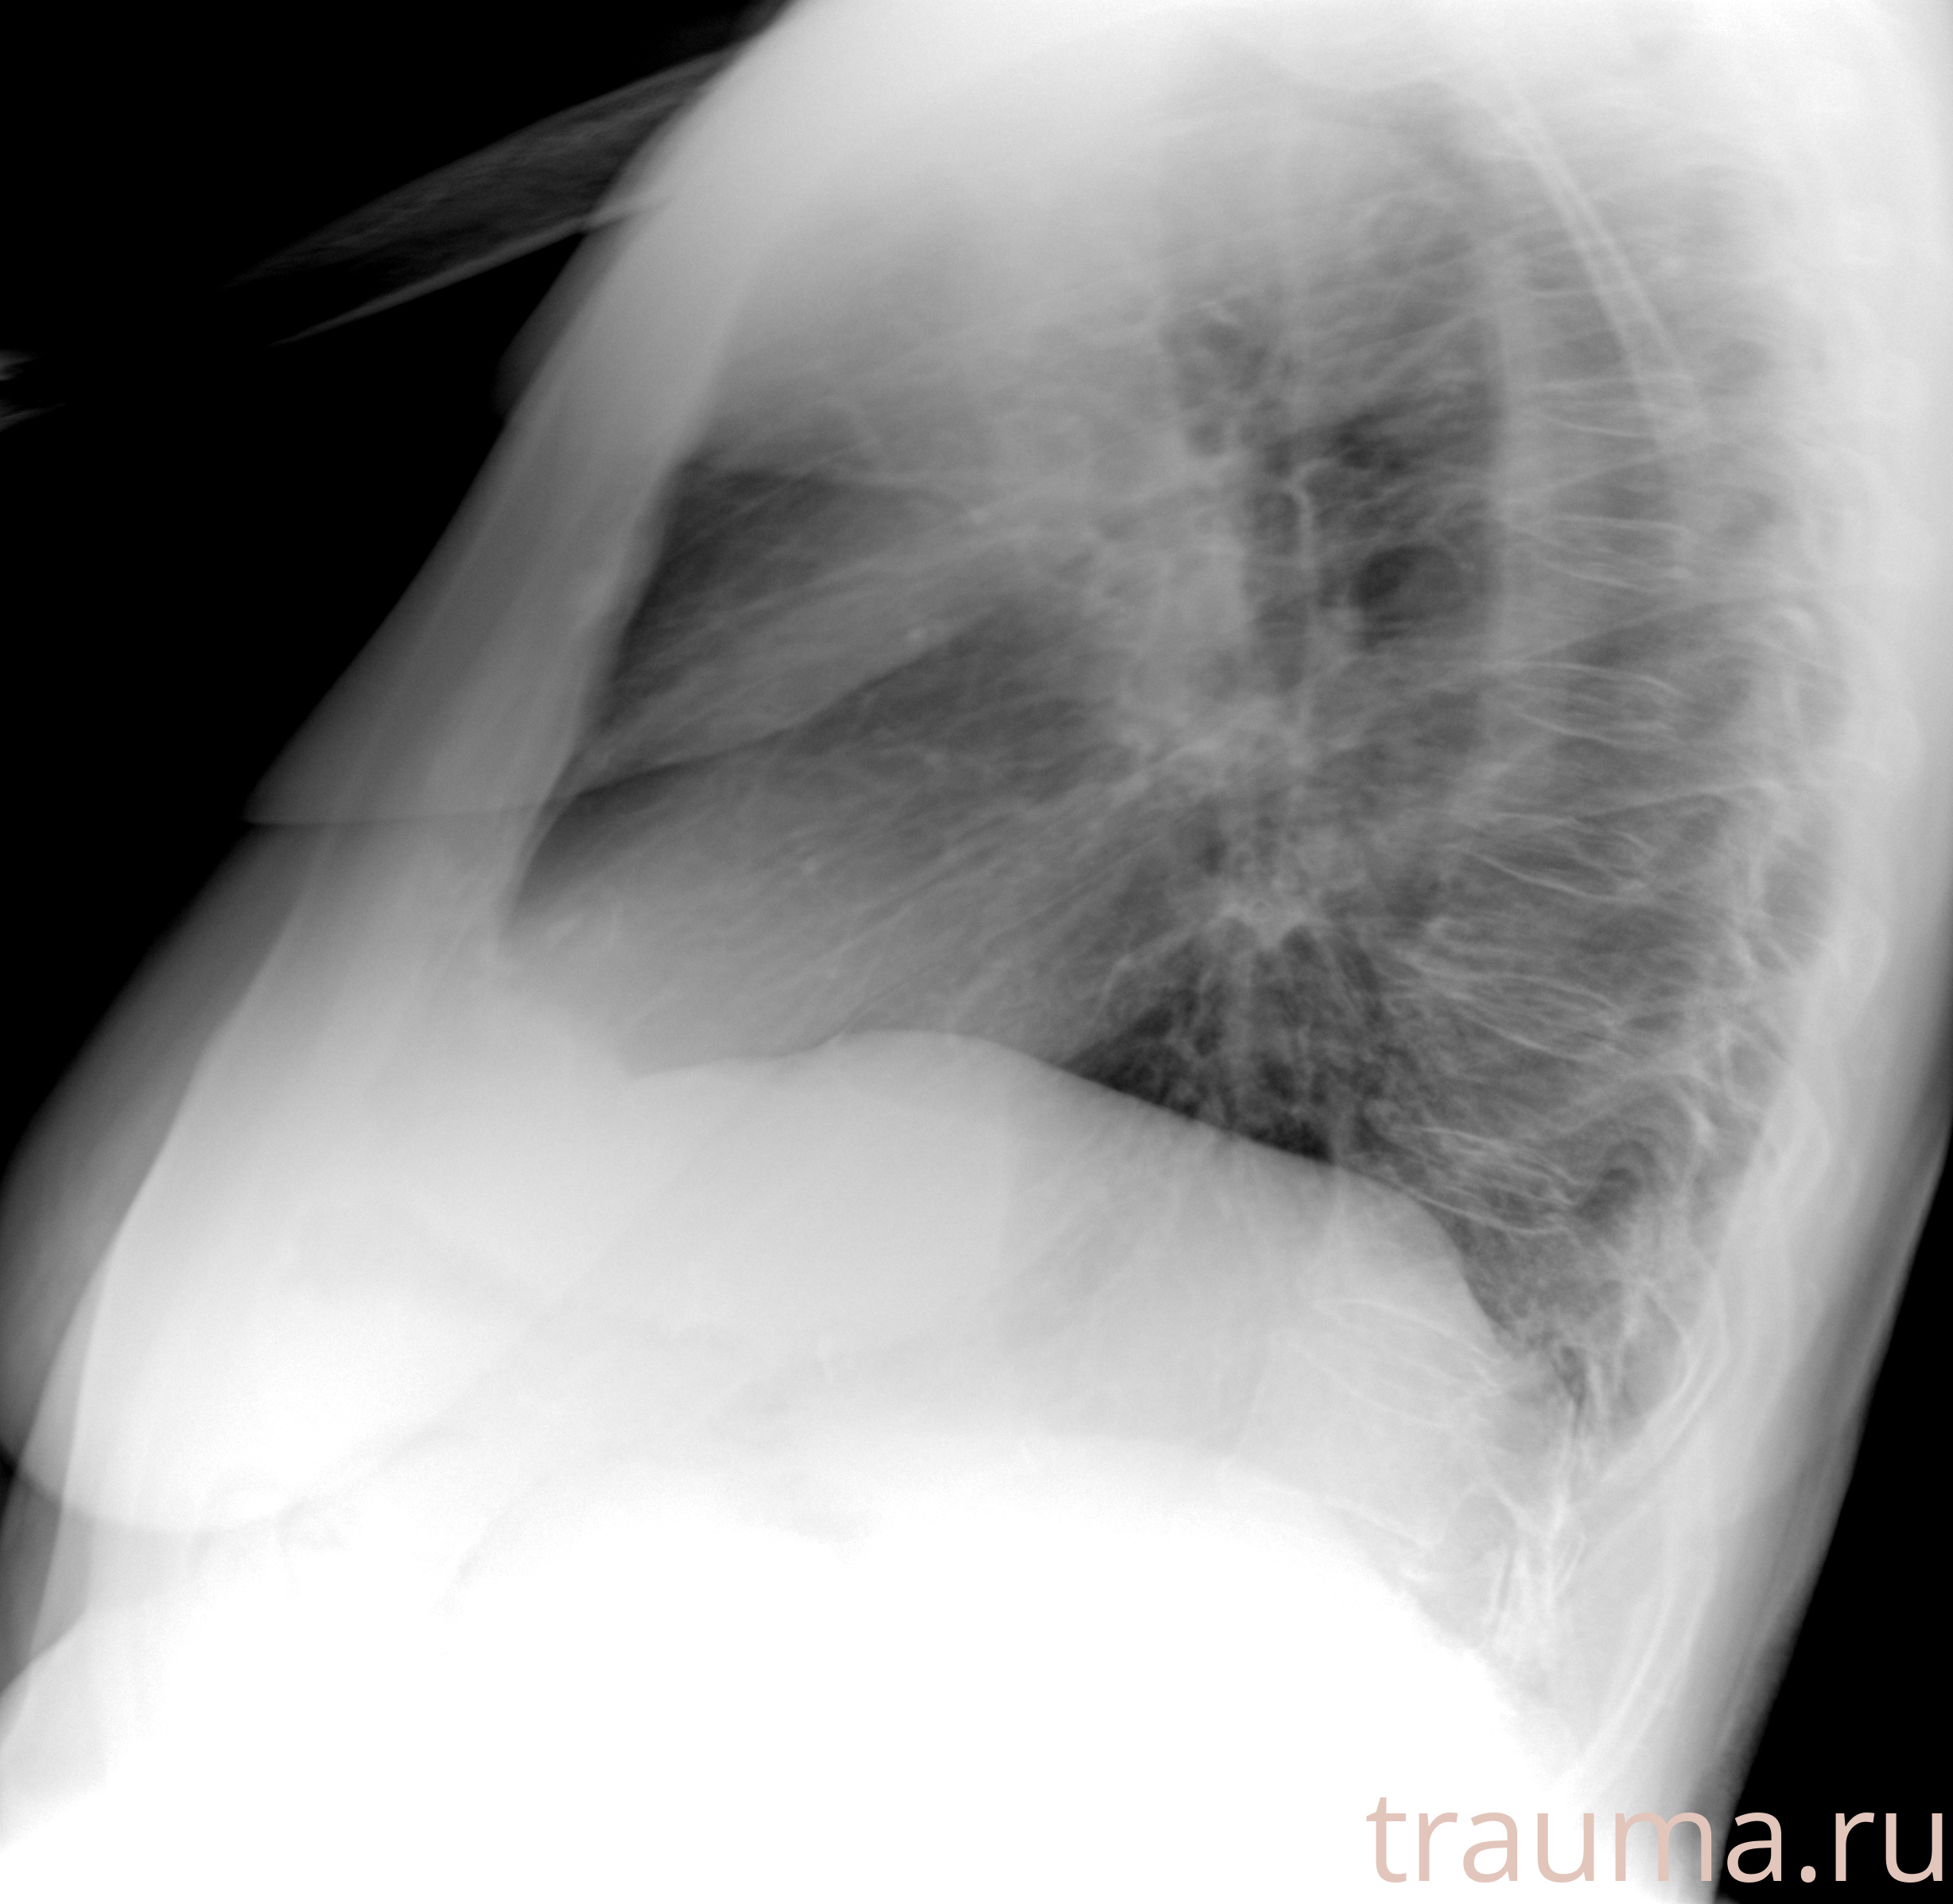

Рентгенограммы

Рентген на дому: по вашему адресу приезжает врач-рентгенолог, травматолог-ортопед с мобильным рентгеновским аппаратом, проводит диагностику травмы или заболевания, делает необходимые рентгенограммы, дает рекомендации по дальнейшему лечению. Получить качественные снимки в домашних условиях возможно благодаря уникальной методике, разработанной МосРентген Центром для института  Склифосовского

при переломе шейки бедра и пневмонии от компании МосРентген Центр - партнера Института имени Склифосовского